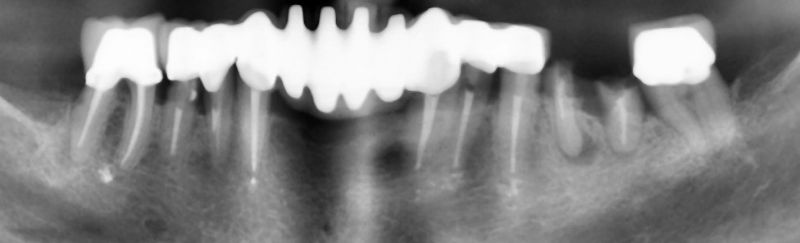

Когато зъбният имплант се постави съобразно с анатомията на костите, то тогава посоката на импланта може да не отговаря на посоката на зъба върху него. Вследствие на това зъбните коронки върху зъбните импланти няма да са естественото им продължение. Получава се по-голям или по-малък ъгъл между зъбен имплант и зъбна коронка. Вследствие на това силите по време на хранене не се предават по оста на зъбния имплант. Възможни са късни усложнения на костта около зъбните импланти – загуба на кост.

В случаите, когато имаме много на брой зъбни импланти /повече от три/. То тогава най-често зъбните импланти се поставят в тяхната хирургична позиция с помощта на хирургични водачи, а протетиката се осигурява от специални надстроики /абатмънти/, наречени multi unit.